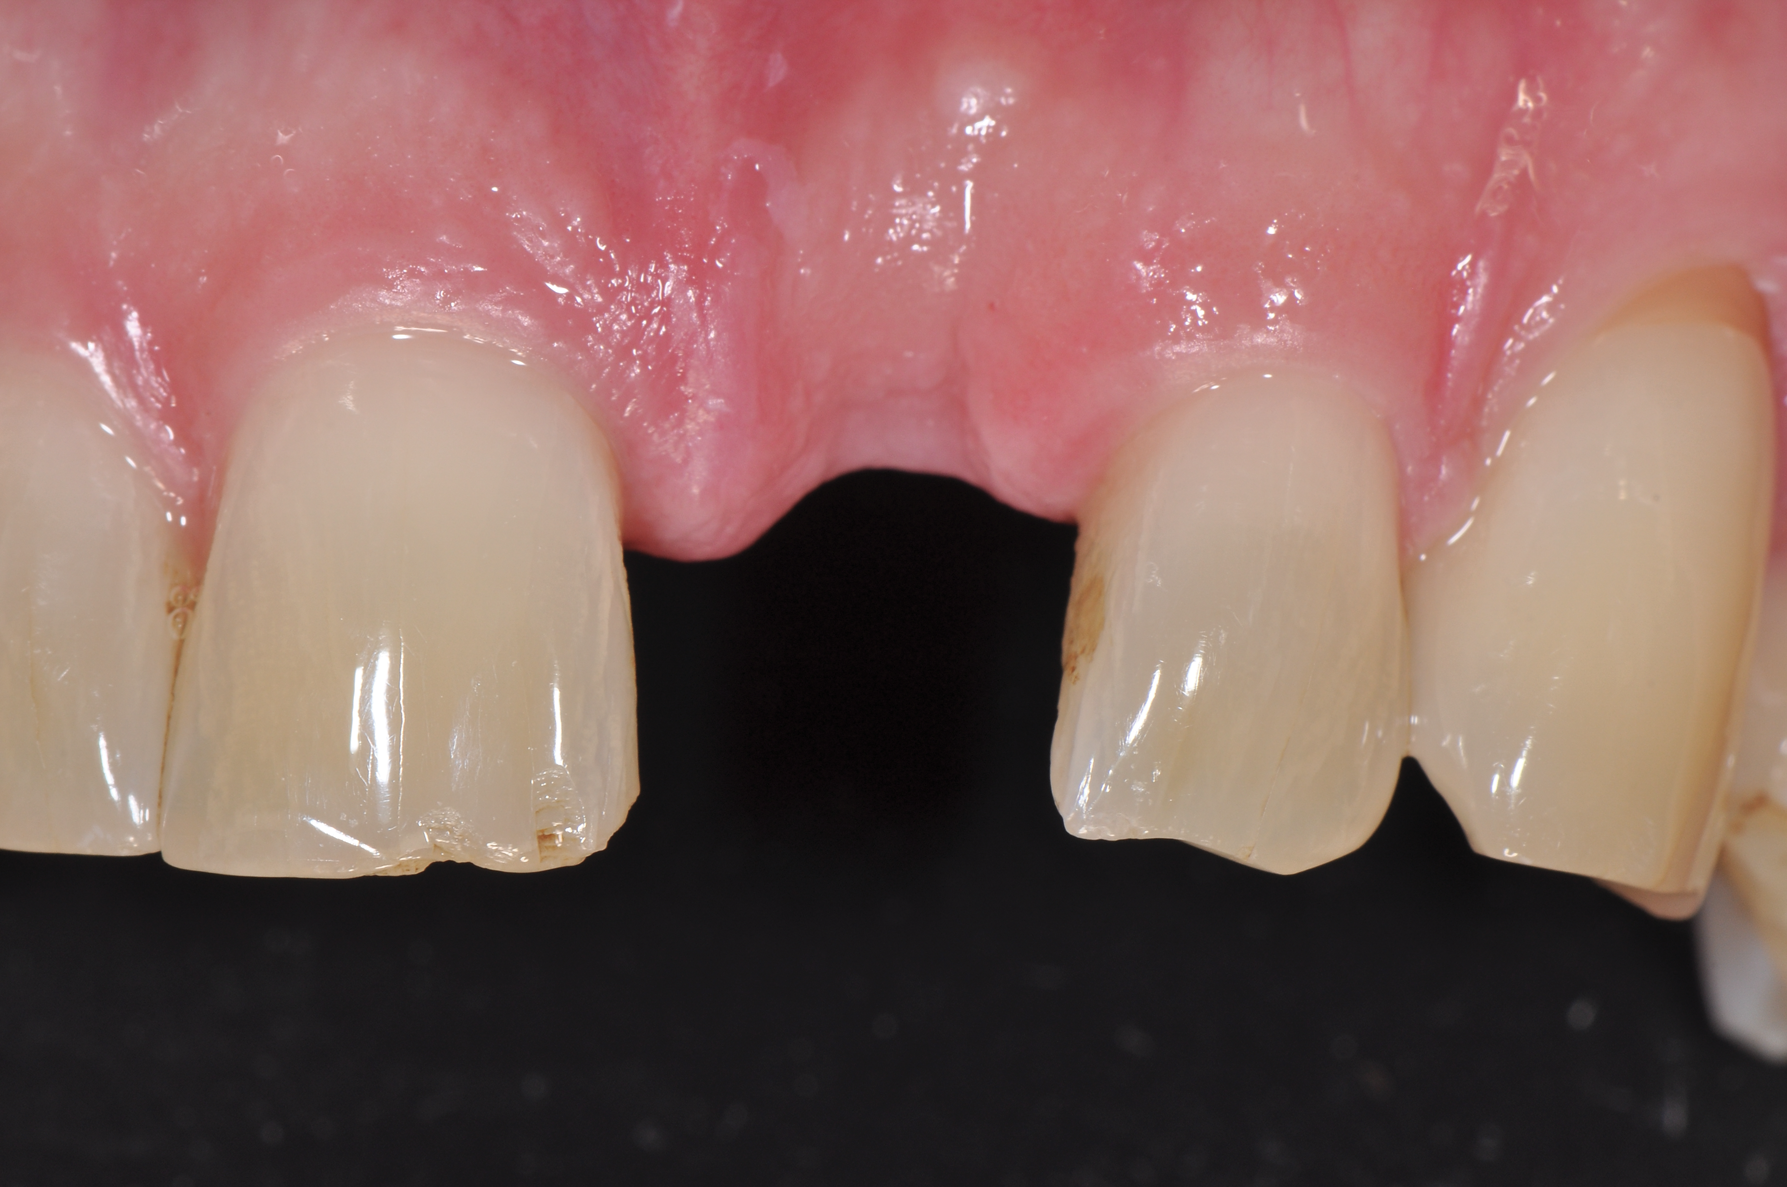

Fig 9. Healed implant site 12 weeks after surgery before re-entry.

Figure 9